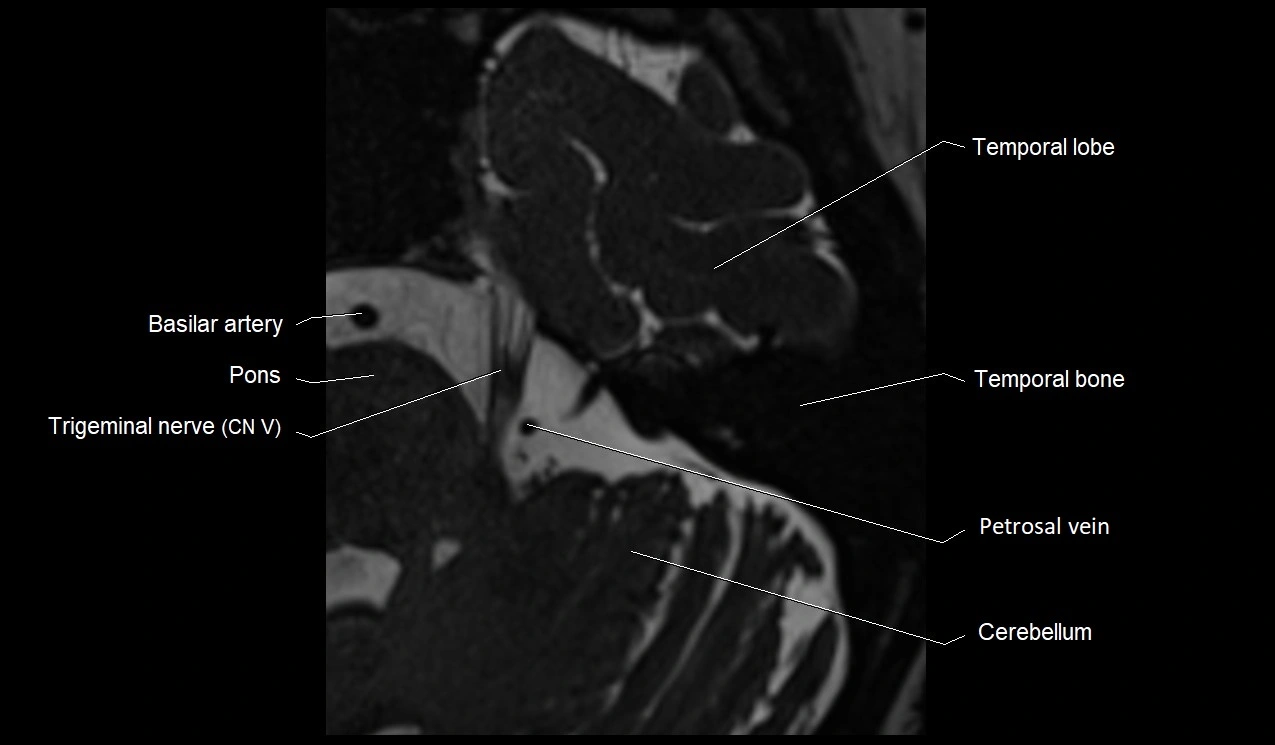

MRI Appearance

• The abducens nerve is a small, thin, linear structure

• Best visualized on high-resolution T2-weighted 3D MRI sequences (e.g., FIESTA or CISS)

• Seen as a hypointense (dark) line running from the brainstem at the pontomedullary junction, traversing the prepontine cistern, and entering Dorello’s canal under the petrosphenoidal ligament, then into the cavernous sinus, and finally the orbit

• May be challenging to visualize in standard MRI due to its small size

• Pathology may be inferred by absence, displacement, or enhancement of the nerve